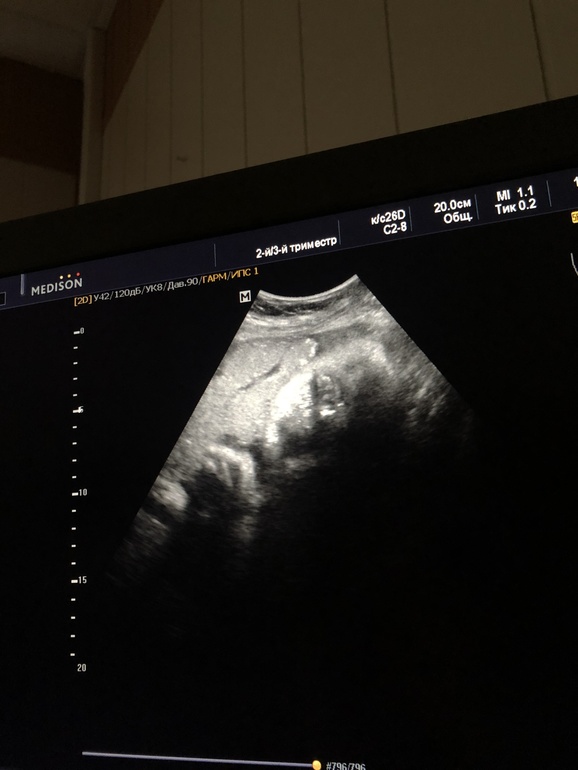

Нам 37 недель, у нас мальчик, на каждом узи говорят, что очень спокойный паренёк, весим 2700гр, развиваемся как положено, часто икаем, максимальный движ наступает ближе к 11-12 ночи) спим до 12 дня, маму не тревожим)

В целом, могу сказать, что беременность прошла наилучшим образом, ну вес, да...+18 кг, но, все говорят - не видно особо, где они прилипли, немного токсикоза с 8 по 14 неделю, кровь на резус конфликт каждые 10 дней, в принципе, это и все дискомфортные моменты) живот сейчас 102 см, ни кто не верит, что у меня 9й месяц...он мне большой и не нужен так то!) на последнем узи сказали что ранее обнаруженное обвитие прошло, шея свободна и пуповину мы держим в руке, в районе головы.